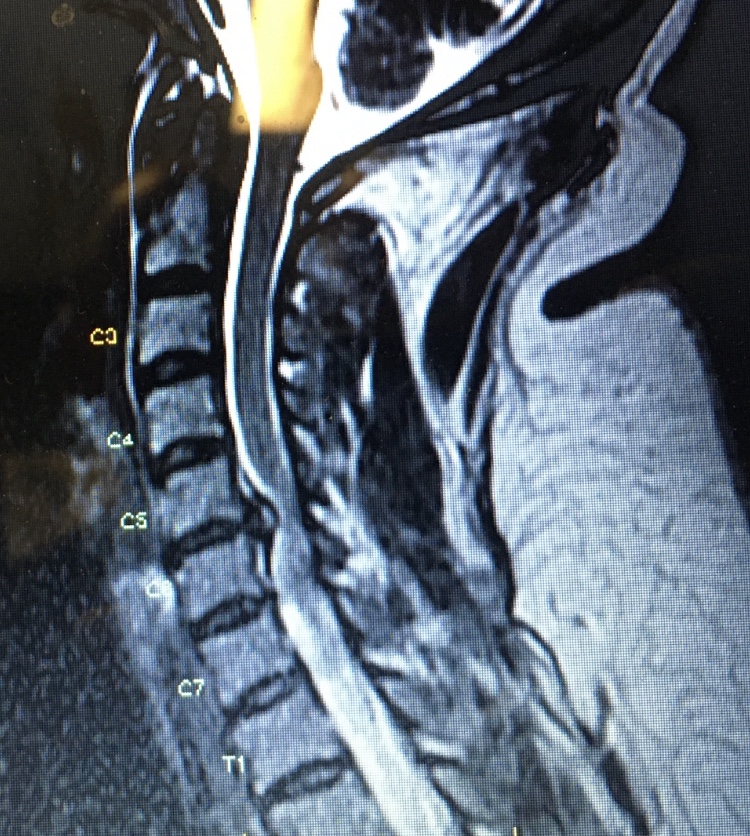

I stepped off the curb in front of the store’s sliding doors and my foot never found solid ground as it rocketed through oil and I fell. I had no idea the combination of events placed in motion that day. The pain instantly showed up in my legs, but the injury was in my neck where my arm had jammed three discs into my spinal cord.

The neurosurgeon later told us any single time I looked over my shoulder to check traffic, or to glance down to click my seatbelt, could have caused my death, or at a minimum, paralysis. She said so few people survive through this dangerous time to make it to surgery; they almost always fall victim to the damage happening in their spinal cord, and yet Amah provided the way. No one understands, and I certainly don’t, how I didn’t sneeze wrong or bend my head to hold my phone, or look fast over my shoulder… all ways my neurosurgeon said would have certainly finished the severing of my spinal cord.

And then came September 2019. The spinal cord compression had exploded my nerves with pain—yet no one knew what it was. ER doctors were turning me away to “manage my pain.” I had one urgent care doctor who told me he believed I was in dangerous trouble of paralysis, but I couldn’t afford the MRI (see yesterday’s post) and had to raise funds for the test.